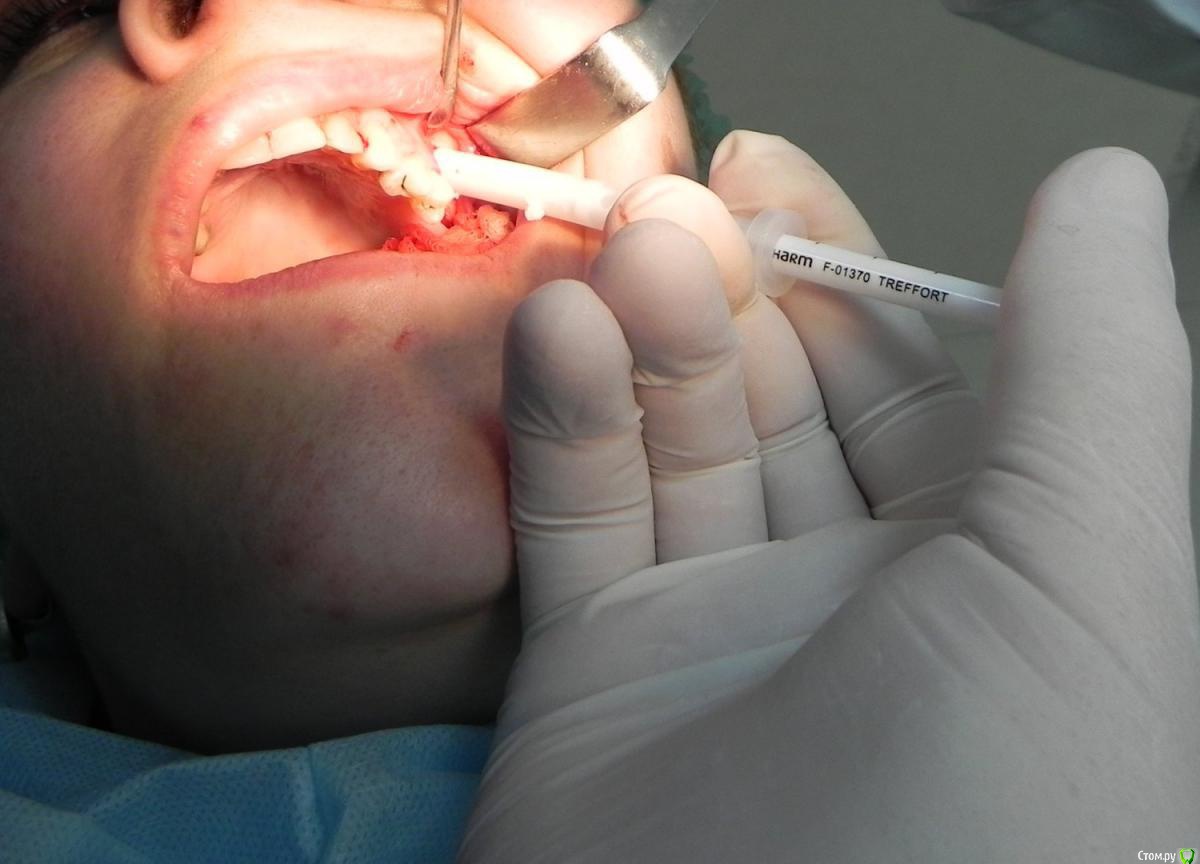

Kostoprav Опубликовано 7 августа, 2015 Поделиться Опубликовано 7 августа, 2015 доступпрепаровка шаровидной костной фрезойпри отслаивании мембраны образовалась маленькая перфа перфорацию" проклеил" коллагеновой мембранойпод мембрану внесен материалмембрана на окноготово может кому из начинающих этот пост полезен будет 1 Ссылка на комментарий

Evikrol Опубликовано 7 августа, 2015 Поделиться Опубликовано 7 августа, 2015 А biooss бывает в шприцах? А то ложкой долго вносить Ссылка на комментарий

AlexanderGudkov Опубликовано 8 августа, 2015 Поделиться Опубликовано 8 августа, 2015 А biooss бывает в шприцах? А то ложкой долго вноситьЕсть байосс пэн, в шприце, но его смачивать все равно надо отдельно Ссылка на комментарий

red_butler Опубликовано 8 августа, 2015 Поделиться Опубликовано 8 августа, 2015 А biooss бывает в шприцах? А то ложкой долго вноситьbiooss pen называется, очень удобная штука. Как эконом вариант, срезаете носик у инсулинового шприца и набиваете его, главное что бы шприц был в индивидуальной упаковке, чаще продают 10 шт в одной Ссылка на комментарий